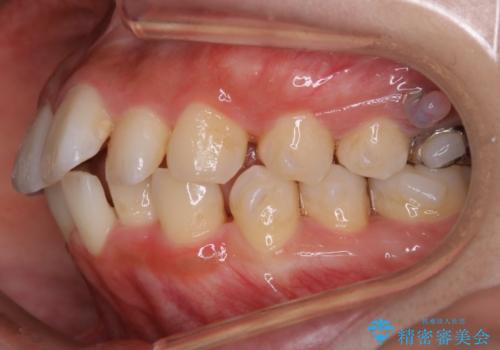

- 歯のガタつきと口元の突出感を主訴に来院されました。

装置の希望がインビザラインだったため、非抜歯でインビザラインの特徴を最大限に生かして行う矯正治療を選択しました。

顔貌写真でも明らかに口の閉じやすさやEラインが改善している様子が分かります。

一般的に口元を下げるための治療というと抜歯矯正を思い浮かべる方が多いかと思います。そもそもガタつきを治したり歯を引っ込めるためのスペースの作り方には大きく分けて4種類の方法があります。

①抜歯 ②歯列の幅の拡大 ③IPR(歯の幅を削って小さくする) ④歯の後方移動 です。

インビザラインの登場により抜歯以外の3種類の方法を効率よく活用することができるようになりました。

そのため、非抜歯でも口元の環境が改善するケースがあります。